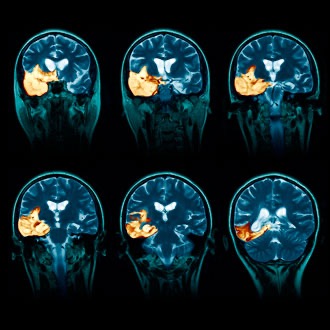

On November 8, 2025, she was rushed to LeBonheur Children's Hospital in Memphis, where she stayed for almost 3 months in ICU in a medically induced coma. On the 40th day she broke through the sedation! She was diagnosed with a rare, life-threatening disease (autoimmune anti-NMDA receptor encephalitis). It causes the body to create antibodies that attack the brain in error, causing the brain to swell and become inflamed. Due to the severe damage done to the brain, she requires neurological rehabilitation, where she is basically learning how to perform the basic functions of life all over again, such as walking, talking, writing, and thinking.